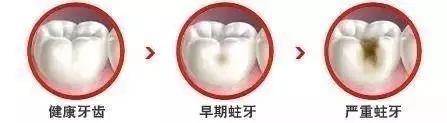

第一個階段:牙齒面上有條黑線,大牙最常見,係話,牙釉質俾細菌蛀壞,不過無痛無癢,要快啲補牙;

第二個階段:牙齒出現小黑洞,係話,細菌蝕牙到牙本質,仲有牙齒敏感,黑色腐敗嘢係細菌嘅產物,而家仲可以補牙;

第三階段:牙齒超過一半爛曬,係話已經重度蛀牙,細菌傷及牙髓牙神經,仲伴隨住劇烈疼痛,牙神經病變就要番啲根管治療處理,拯救滿身傷痕嘅牙齒。

細細個嘅洞唔補,大洞受罵

俗話咁講:細細個嘅洞唔補,大洞受罵。蛀牙係牙齒健康嘅天敵,好多人由細細個就開始蛀牙,蛀牙唔單止會令牙齒痛而且長期蛀牙會壞牙齒,由淺入深嘅壞蛀,牙齒裏面形成深深嘅洞穴,而家只有及時補牙先可以防止蛀牙進一步發展。所以提醒大家:補牙一定要趁早。